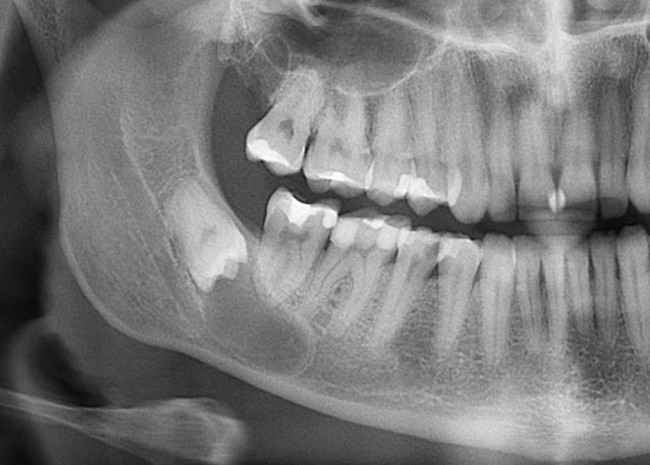

Скажите, имеет ли смысл думать об удалении/сохранении такого зуба:

Конечно нет! Тем более, ситуация аналогична предыдущему случаю. Удаляем. Без сожалений!

И вот картинка через год:

Как видите, все просто.